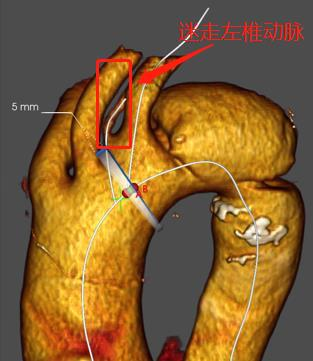

术前CTA:

治疗车怎么推「弓部重建直通车」鄂尔多斯市中心医院康巴什部介入科运用Castor®分支型支架联合预开窗技术治疗Stanford B型胸主动夹层_https://www.jmylbn.com_新闻资讯_第3张

CTA三维重建

1、根据CTA显示,患者为Stanford B型主动脉夹层合并迷走左椎动脉,近端累及左锁骨下动脉(LSA),远端累及腹腔干动脉及肠系膜上动脉起始部,对于累及弓部的夹层,应优先考虑处理弓上病变,封堵第一破口;

2、根据CTA平扫显示,患者为迷走左椎动脉,迷走左侧椎动脉是指左侧椎动脉不是始发于LSA,而是始发于主动脉弓部,是一种较为少见的先天性发育异常的解剖异常,该病例迷走左椎动脉始发于左颈总动脉(LCCA)与LSA之间。

治疗车怎么推「弓部重建直通车」鄂尔多斯市中心医院康巴什部介入科运用Castor®分支型支架联合预开窗技术治疗Stanford B型胸主动夹层_https://www.jmylbn.com_新闻资讯_第4张

迷走左椎动脉

3、若将支架近端锚定在LCCA后缘,常规支架会遮盖迷走左椎动脉与LSA,由于患者为均势供血,遮盖迷走左椎动脉与LSA,会引发左上肢缺血与提高脑梗等疾病的风险,故需重建迷走的左椎动脉与LSA;